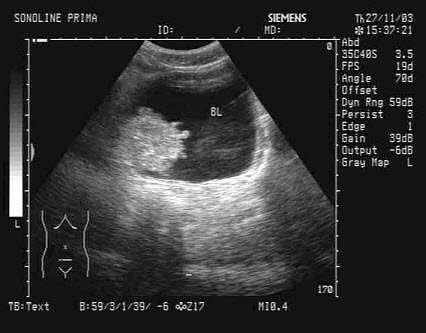

52、单项选择题

女性,29岁,停经28周,产前超声检查如图,最可能的诊断为()

A.胎儿畸形,脑积水

B.胎儿畸形,腹壁裂

C.胎儿畸形,室间隔缺损

D.胎儿畸形,无脑儿

E.胎儿畸形,露脑畸形